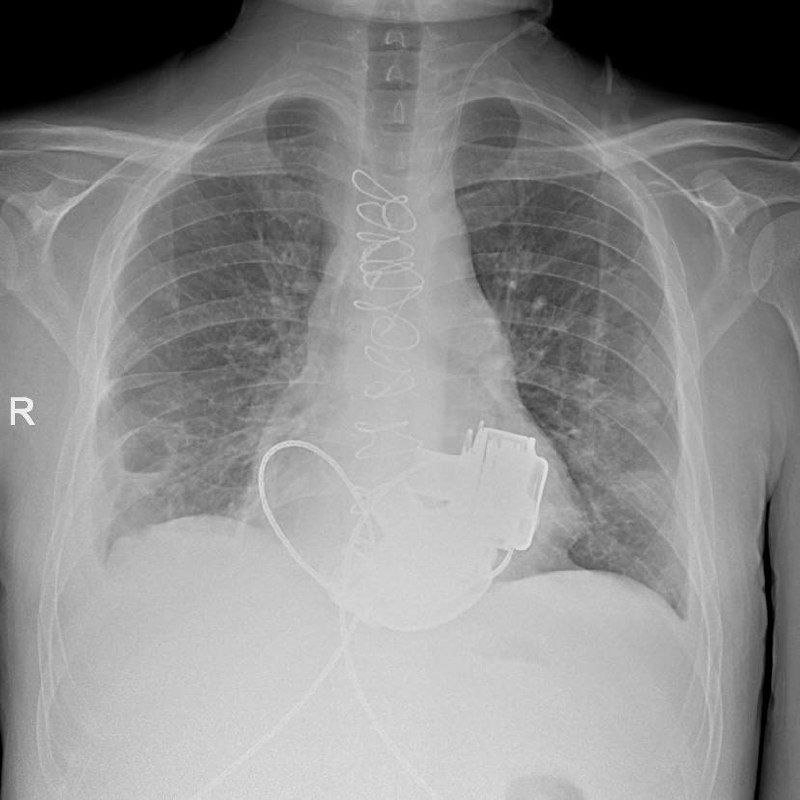

В Мариинской больнице готовится к выписке уникальный пациент, который с недавних пор живет без пульса. Как сообщает учреждение в своем телеграм-канале, в конце ноября 2025 пациенту впервые в России имплантировали сразу два искусственных желудочка сердца. Когда мужчина поступил в больницу, показатели работы его сердца были такими, “будто человек уже не жив, а мертв”. При этом из-за ряда осложнений трансплантация целого сердца была невозможной. Главный врач больницы Игорь Реутский принял решение об имплантации искусственных желудочков. Операция продолжалась около 4 часов.

Рентген пациента с искусственными желудочками сердца. Фото: Телеграм-канал Маринской больницы